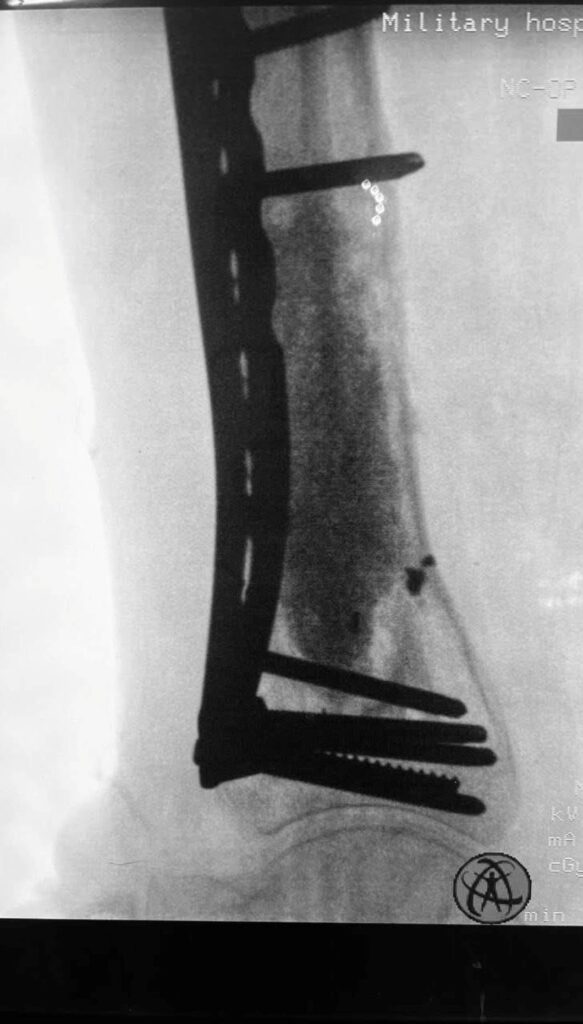

Минно-взрывное ранение военнослужащий (сейчас демобилизованный) получил в феврале этого года. Сначала выполнено 6 операций, направленных на первый этап сохранения руки (аппарат внешней фиксации и «чистки раны»). Несмотря на то, что в ране поселилась «военная» бактерия (американские хирурги называют её и еще одну – ацинетобактер – «иракская бактерия» или «болезнь ветеранов»), украинским врачам удалось с инфекцией справиться.

Поэтому вместе с фиксацией этой реально разрушенной плечевой кости (см рентгенограмму) пластиной из минидоступов, мы с Vasyl Parii и Денисом Долгушем не стали одномоментно делать и массивную костную пластику. Взяли ткани снова на посев. Если посев будет стерилен, то следующим этапом сделаем пластику. Если нет, – то вновь проведем антибактериальную мощную терапию.